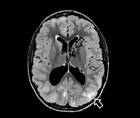

In addition to muscular abnormalities, numerous other systems are involved in LOPD. Cerebrovascular involvement including stroke, aneurysm, and hemorrhage has been described and, although it is not fully understood, may be related to glycogen deposition in the smooth muscle component of cerebral arteries.12 A study of over 200 individuals found cerebral aneurysmal rupture resulted in 3% of deaths, although the study population included people with atypical forms of infantile Pompe disease.3 Small fiber neuropathy has been described, and a study reported neuropathic involvement in 50% of the people who reported pain and discomfort or temperature alterations.9